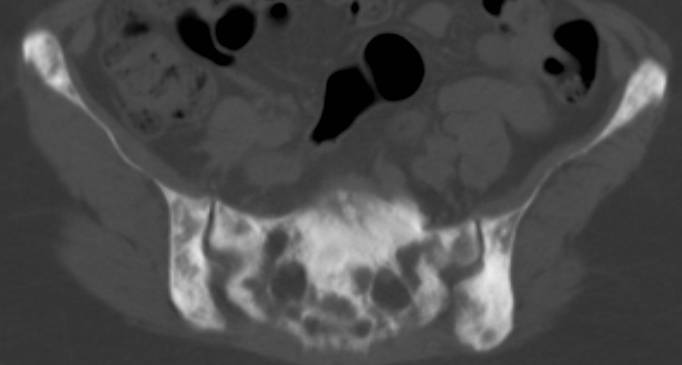

• Some bone cancers make the bone look " too white" called osteoblastic mets of the pelvis or osteoblastic spine , CT of blastic mets here and here and here

• some cancer make "black holes" or lytic mets (another lytic lesion), renal cell cancer causes lytic lesions (go here), and see CT showing diffusely mottled bone here and here